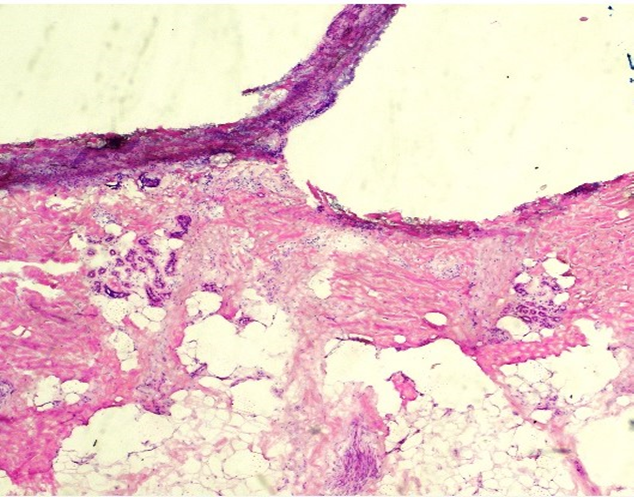

H&E - BMT Scheme

This is an excellent preparation of a BMT biopsy, with balanced H&E staining, good chromatin detail, and selective staining of cell types within the bone marrow tissue. This slide was scored 9/10 at assessment.